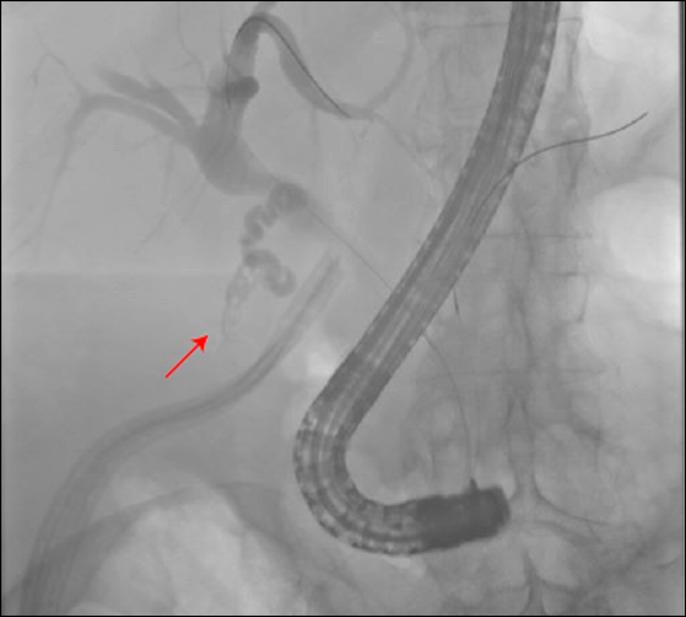

Cystic duct stump leak remains a difficult clinical problem despite advancements in endoscopic techniques. When these minimally invasive strategies fail, patients are often subject to high morbidity and mortality associated with open surgical exploration. We report the successful treatment of persistent biliary leak from the cystic duct stump following cholecystectomy using percutaneous transabdominal access of the cystic duct and coil embolization.

尽管内镜技术有所进步,但胆囊管残端漏仍是一个棘手的临床问题。当这些微创策略失败时,患者往往面临与开放手术探查相关的高发病率和死亡率。我们报告了经皮经腹进入胆囊管并进行线圈栓塞术成功治疗胆囊切除术后胆囊管残端持续性胆漏的病例。